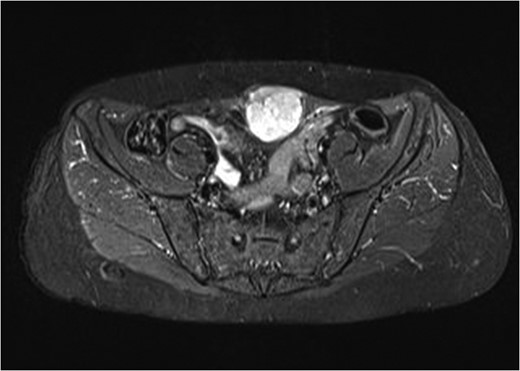

Complete blood laboratory tests, including tumor markers, showed values within normal limits. An abdominal computerized tomography and magnetic resonance imaging were performed; the latest revealed that the mass presented dimensions of 6.7 × 4.9 × 3.5 cm3, was located on the left rectus abdominis muscle, whereas no further intra-abdominal pathologic conditions were found (Figs 1 and 2). After adequate information and written consent, the patient was submitted to surgical excision of the mass.